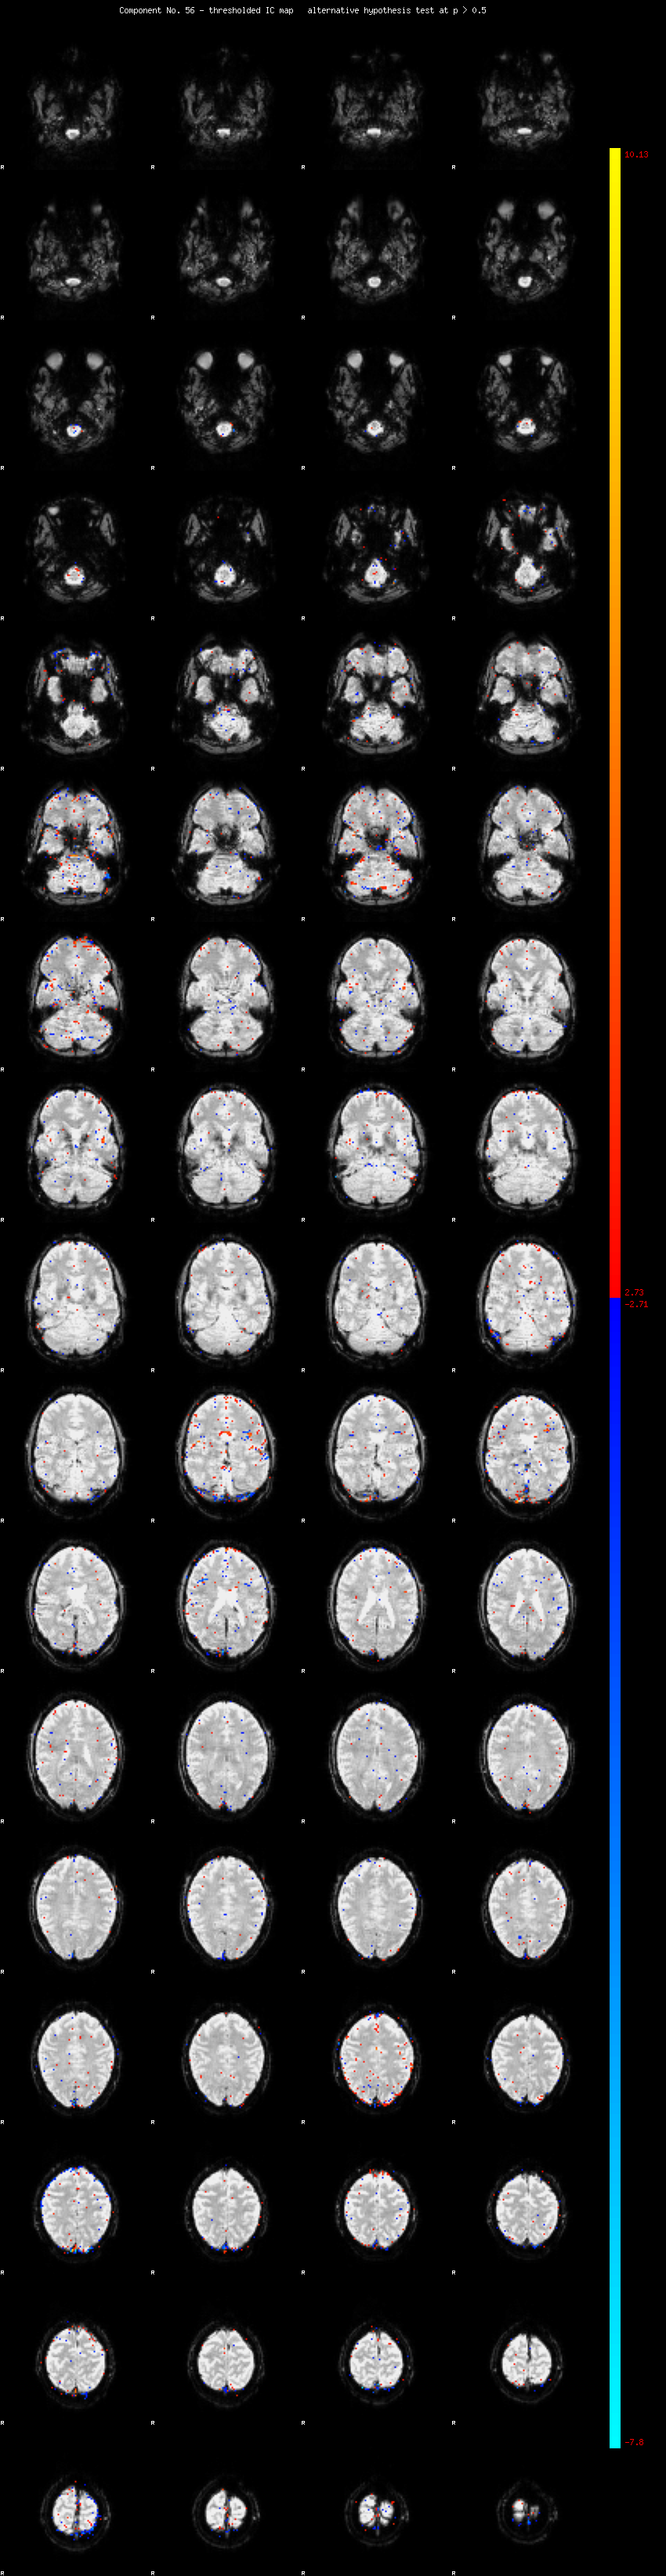

MELODIC Component 56

0.88 % of explained variance;     0.58 % of total variance